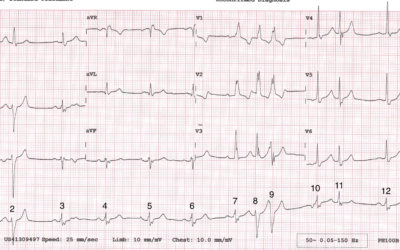

I don’t have any clinical information in relation to this month’s ECG, but what I’m interested in is the rhythm and conduction. I don’t think it’s quite as straightforward as it first appears and I’m not absolutely sure of everything that’s going on. I’ve numbered the...

Dr Dave Richley ECG of the Month – August 2021

This ECG was recorded at 25mm/s from a 72 year old male who was complaining of a prolonged period of chest pain at rest. He has a history of diabetes and hypertension. How should the ECG be interpreted? Dr Dave Richley, Associate Lecturer Newcastle University...